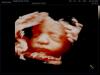

На какой неделе делать 3D УЗИ для четких снимков ребенка?

На какой неделе сходить на 3D узи, чтобы получились уже красивые снимки, где будет чётко видно сына? 🐬 Я уже делала, но только очертания видны.

На 28 🥹😍

Такие буськи там

Уже с такой внешностью и рождаются не чего не меняется